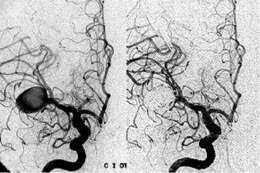

• Angiografía con sustración

Angiografía con sustración

En este año se crea una nueva herramienta en imagenes.

Por sustracción digital en (3D,ASD).

Lo que permitió un gran avance para los profesional (radiólogos) neuro-intervencionista, obteniendo una mayor definición y precisión a la hora de realizar el estudio.